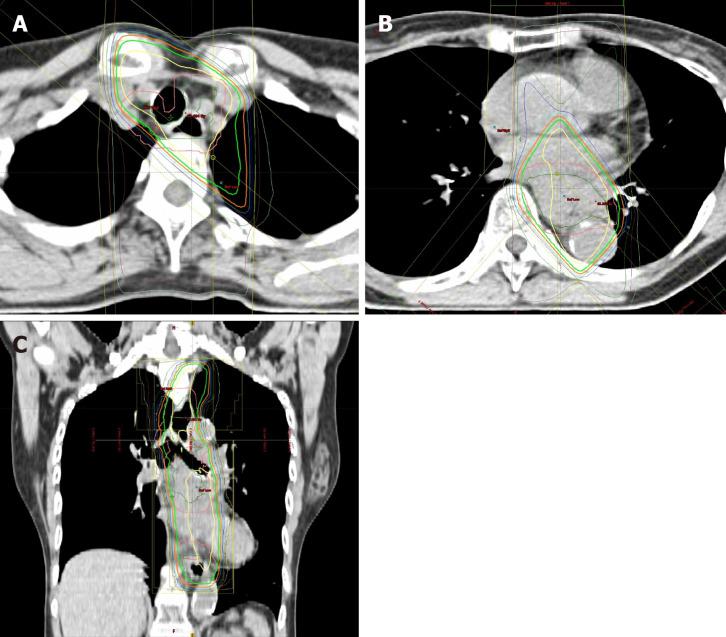

We report a successful case of a 59-year-old female with unresectable locally advanced T4 ESCC treated by two additional courses of chemotherapy with CF after induction chemotherapy with docetaxel, cisplatin and fluorouracil (DCF) followed by dCRT. Initial esophagogastroduodenoscopy (EGD) detected a type 2 advanced lesion located on the middle part of the esophagus, with stenosis. Computed tomography detected the primary tumor with suspected invasion of the left bronchus and 90° of direct contact with the aorta, and upper mediastinal lymph node metastasis. Pathological findings from biopsy revealed squamous cell carcinoma. We initially performed induction chemotherapy using three courses of DCF, but the lesion was still evaluated unresectable after DCF chemotherapy. Therefore, we subsequently performed dCRT treatment (CF and radiation). After dCRT, prominent reduction of the primary tumor was recognized but a residual tumor with ulceration was detected by EGD. Since the patient had some surgical risk, we performed two additional courses of CF and achieved a clinically complete response. After 14 mo from last administration of CF chemotherapy, recurrence has not been detected by computed tomography and EGD, and biopsy from the scar formation has revealed no cancer cells.

我们报告了1例成功治疗的病例,患者为59岁女性,患有不可切除的局部晚期T4期ESCC,在接受多西他赛、顺铂和氟尿嘧啶(DCF)诱导化疗后,再接受两周期CF化疗,随后进行同步放化疗。最初的食管胃十二指肠镜检查(EGD)发现食管中段有一处2型进展期病变并伴有狭窄。计算机断层扫描发现原发性肿瘤,怀疑侵犯左支气管,与主动脉直接接触90°,并有上纵隔淋巴结转移。活检病理结果显示为鳞状细胞癌。我们最初采用三周期DCF进行诱导化疗,但DCF化疗后病变仍被评估为不可切除。因此,我们随后进行了同步放化疗(CF和放疗)。同步放化疗后,原发性肿瘤明显缩小,但EGD检查发现有残留肿瘤伴溃疡形成。由于患者存在一定的手术风险,我们又进行了两周期CF化疗,实现了临床完全缓解。在最后一次CF化疗后14个月,计算机断层扫描和EGD检查未发现复发,瘢痕形成部位的活检未发现癌细胞。